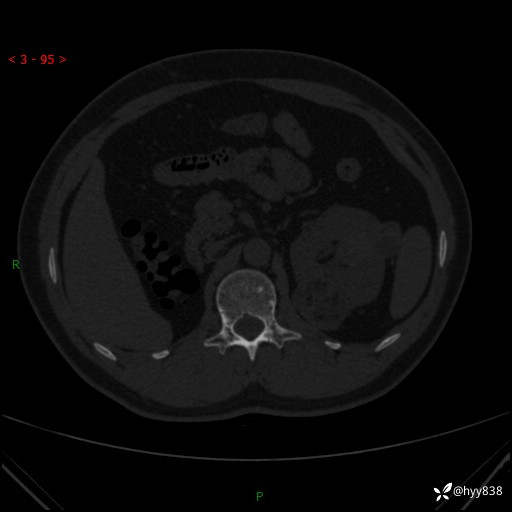

病例年轻小伙,早早的就切除了右侧肾脏,他怎么了---结果公布~

患者性别:男

患者年龄:28岁

简要病史:右肾肿瘤术后,常规复查

辅助检查:CT

临床诊断:右肾肿瘤术后

腹部CT+颅脑CT平扫

骨窗